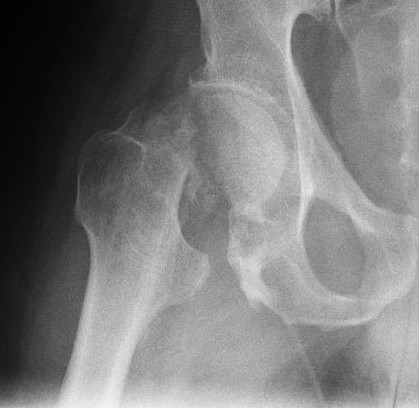

Ziel: In dieser Studie sollte die Plättchen-reiche Plasma Therapie (PRP) bei Patienten mit Hüftarthrose getestet werden. Es handelt sich um eine kontrollierte, randomisierte Studie, die in einer orthopädischen Klinik in Bologna durchgeführt wurde.

Methode: Patienten mit primärer Hüftarthrose im Alter zwischen 18 bis 65 Jahren wurden eingeschlossen. Ausgeschlossen waren Patienten mit rheumatologischen Erkrankungen, Infektionen, Störungen des Immunsystems und starken Deformierungen. Der erste Endpunkt nach der Injektionstherapie war die Veränderung der Schmerzen nach 2, 6 und 12 Monaten. (gemessen mit visueller Analogskala VAS im Hüftgelenk). Sekundäre Endpunkte waren der Harris Hip Score und der WOMAC Hüftarthrosescore.

Resultate: 111 Patienten wurden in 3 Gruppen eingeteilt. Diese erhielten im wöchentlichen Abstand 3 Injektionen in die Hüfte unter Ultraschallkontrolle. 44 Patienten waren in der PRP Gruppe, 31 Patienten in der PRP und Hyaluronsäuregruppe (HA) und 36 Patienten in der Hyaluronsäuregruppe. Bei den Nachkontrollen war der VAS Score in der PRP Gruppe 21 (CI 15-28), in der PRP und HA Gruppe 35 (CI 26-45) und in der HA Gruppe 44 (CI 36-52). Nach 12 Monaten war jedoch kein Unterschied mehr festzustellen (1).

Schlussfolgerung: Diese Resultate deuten an, das die PRP Therapie zu einer schnelleren Schmerzreduktion als die Hyaluronsäuretherapie führen könnte. Die Studie weist jedoch erhebliche Mängel auf, da die Patienten und die behandelnden Aerzte nicht verblindet waren. Zudem gab es keine echte Kontrollgruppe und die zusätzliche Schmerzmedikation wurde nicht korrekt erfasst. Die sogenannte Plättchen-reiche Plasma Therapie stellt deshalb immer noch eine unbelegte experimentelle Therapieoption dar. Zudem ist sie mit dem Risiko eines möglichen Gelenksinfekts bei der intra-artikulären Injektion behaftet.